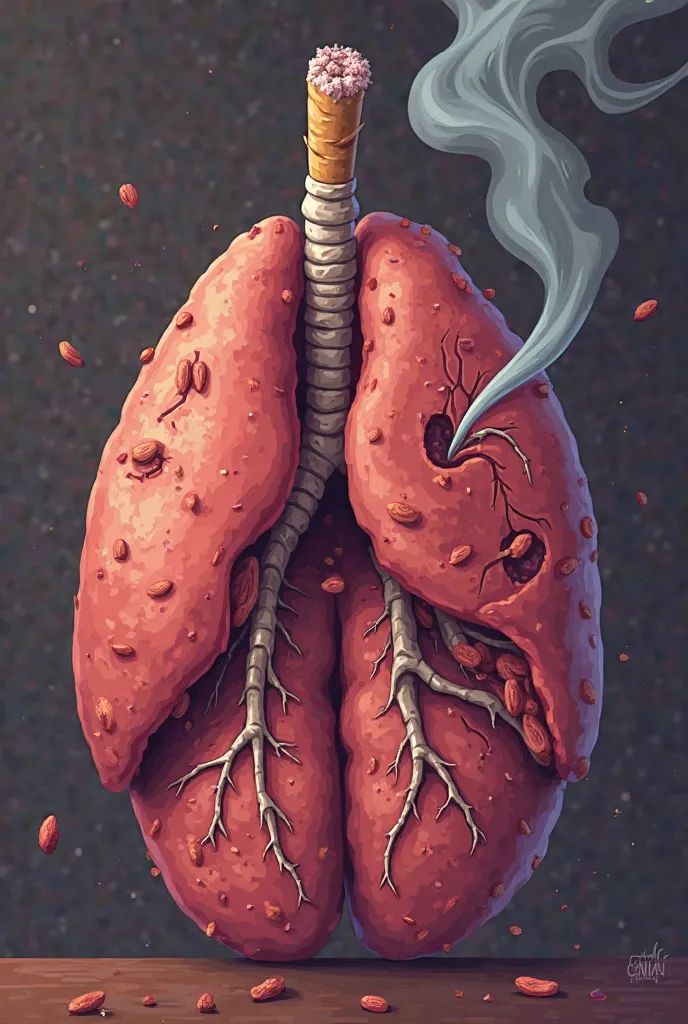

Generate a lungs, the right side lungs is healthy vibrant color surrounded with

Generate a lungs, the right side lungs is healthy vibrant color surrounded with fresh air. On the left side make the lungs damage or pollution of elements in smoking. Add some symbols of no smoking in the pulution part, and add some clean air in the right side lungs

Generate a lungs

the right side lungs is healthy vibrant color surrounded with fresh air

On the left side make the lungs damage or pollution of elements in smoking

Add some symbols of no smoking in the pulution part

and add some clean air in the right side lungs